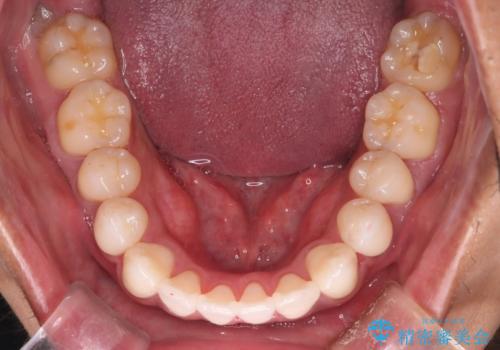

IPR(歯と歯の間を削る処置)と顎間ゴムを行い歯並びを整える治療計画を立てました。

早く終わらせたいとの事でしたが、ゴム掛けを頑張っていただいたので

9ヶ月という短い期間で治療が完了しました。

矯正後は保定経過とメンテナンスで経過を見ていきます。